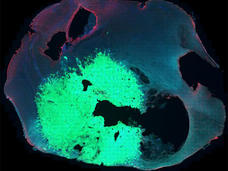

Modified Stem Cells Deliver Chemotherapy to Metastatic Tumors

Researchers have used modified stem cells to deliver a cancer drug selectively to metastatic breast cancer tumors in mice. The stem cells target metastatic tumors by homing in on the stiff environment that typically surrounds them.